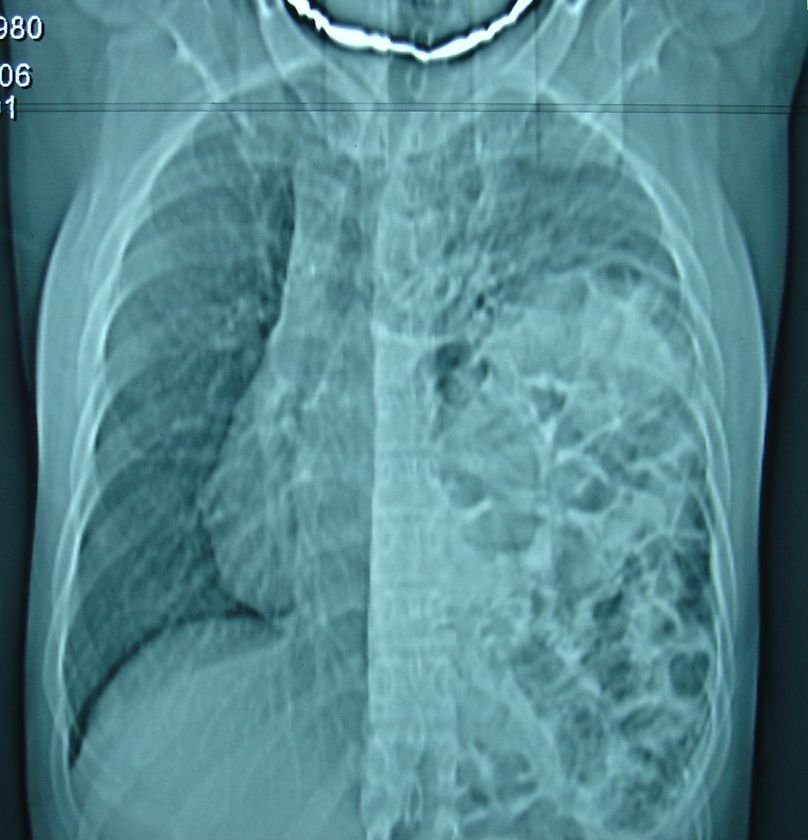

Dəqiqləşdimə

Difrqamal yırtıqların dəqiqləşdirmək üçün kontrastlı müayinələr, bəzən də endoskopik müayinə aparmaq lazım gəlir. Kontrastlı müayinədə mədə və bağırsaqların döş boşluğunda olması diaqnozu dəqiqləşdirir. KT daha informativdir. Təcili vəziyyətlərdə nazoqastrik zondun yerini rentgenlə təyin etməklə də postravmatik yırıtıqları müəyyənləşdirmək olar.

Bəzi hallarda diafrqamal yırtıqları atelektaz, diafraqma relaksasiyası və törəmələrdən diferensasuya etmək lazım gələ bilir. Belə hallarda KT ən vacib müayinə sayılır.

Diaqnozu rentgenoloji müayənə və KT ilə dəqiqləşdimək olar. Müalicəsi cərrahi bərpadan ibarətdir, laparotomiya, torakotomiya və laparo-torakoskopik yollarla bərpa edilə bilər.

Şəkil 3. Diafraqma yırtığı